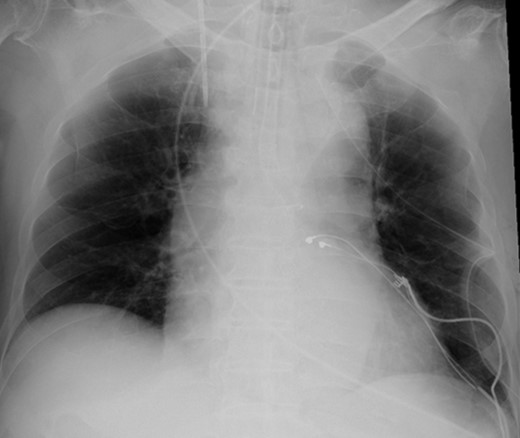

According to the current guideline for pacemaker infection, it was decided to remove the whole pacemaker system, including the two leads. Since implantation of new transvenous leads seemed undesirable because of ongoing active endocarditis, it was decided to implant epicardial leads on the left atrium and left ventricle via a left mini thoracotomy. Because the patient had complete AV block without any spontaneous R wave, a new DDD pacemaker system was implanted first. The atrial lead was implanted on the appendage of the left atrium, and the ventricular lead was implanted onto the lateral wall of the left ventricle near the first obtuse marginal branch (Fig. 3). The old infected pacemaker system was then explanted by percutaneous extraction.

After the operation, the patient recovered rapidly. Of note, postoperative transthoracic echocardiography showed dramatically improved LV function, with EF of 56%. Moreover, dyssynchrony disappeared. On the other hand, the vegetation at the tricuspid valve remained unchanged. He was transferred to a territorial hospital for further therapy with antibiotics on the seventh postoperative day. Now, 3 years after surgery, the patient is doing very well without any sign of heart failure.